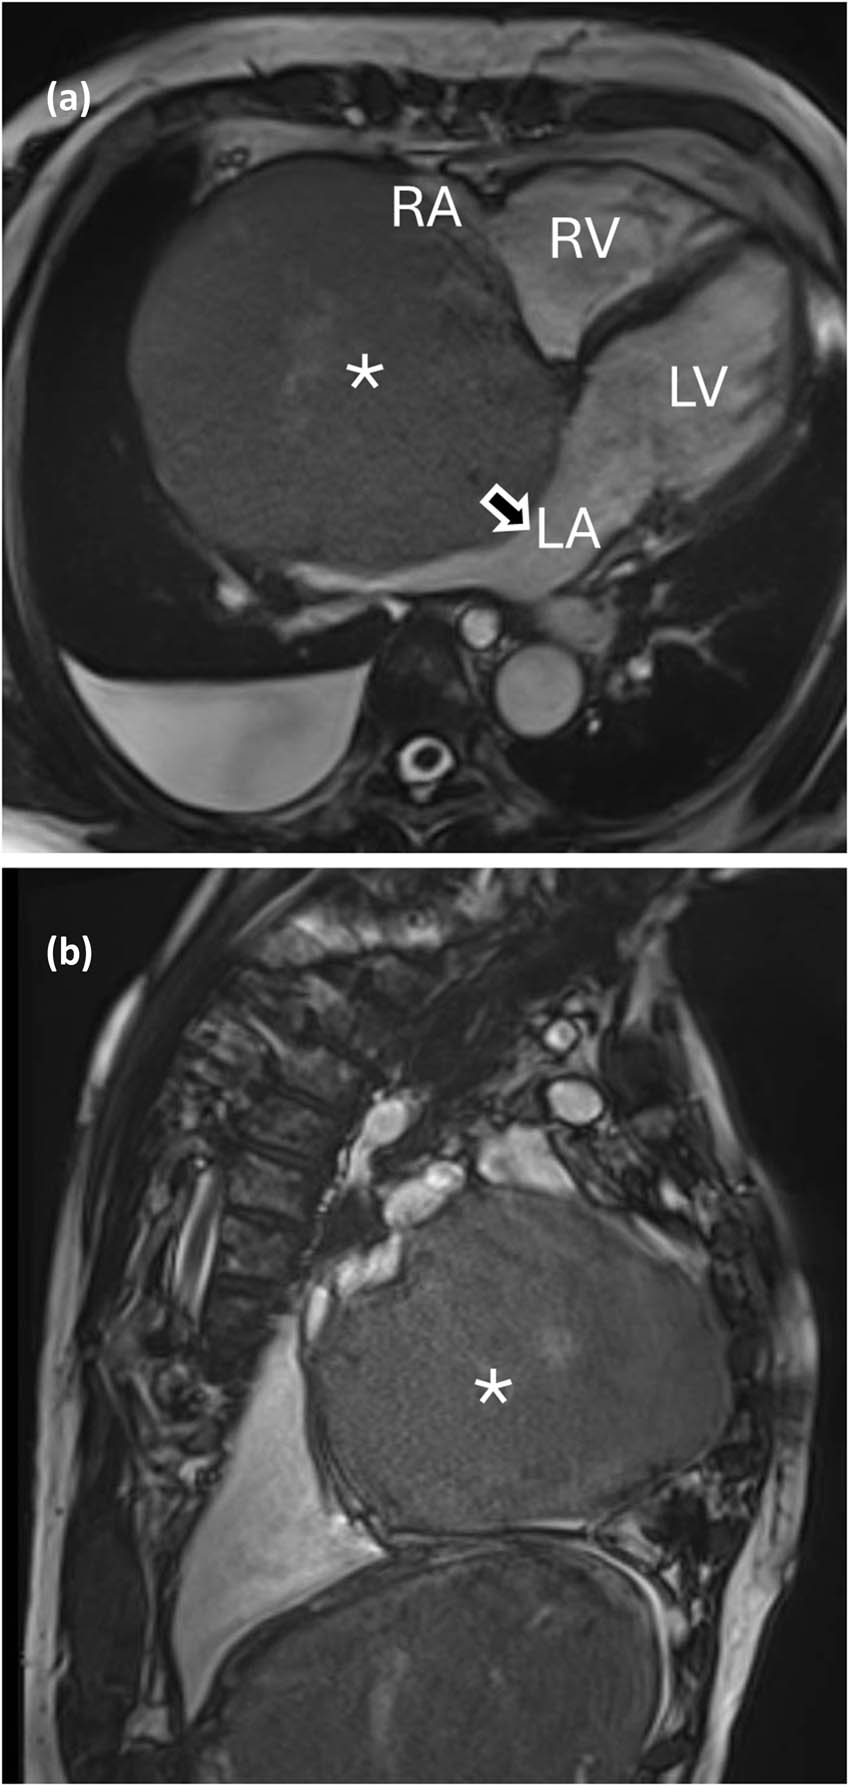

A 72-year-old woman, active smoker with a past medical history of COPD was admitted after 6 months of abdominal swelling related to ascites, swollen ankles and mild jaundice. The patient had no history of alcoholism. Liver ultrasonography showed a cirrhotic liver pattern with nodular hepatic contour and changes in volume distribution, without signs of hepatic hemangiomas. Blood tests revealed high bilirubin levels (2 mg/dl) with predominant direct bilirubin. Gastroscopy showed esophageal varices without bleeding. She reported no pain or dyspnea. Lung examination was unrevealing. Diuretic treatment was started. The electrocardiogram showed sinus rhythm, with signs of right ventricular strain. Chest computed tomography scan and magnetic resonance imaging (MRI, Figure 1) of the chest showed pleural effusion in the right side and a mass of 130 mm in the right atrium. Echocardiography showed a voluminous mass (130 mm × 110 mm) in the right atrium attached to the interatrial septum obstructing blood venous return through the inferior vena cava which appeared dilated. Troponine I values were negative. An ultrasound-guided tranjugular biopsy of the cardiac mass was performed, which excluded malignant mesenchymal tumors, sarcomas or organized clots. Histological examination suspected atrial myxoma. A positron emission tomography scan revealed heterogeneous moderate tracer’s accumulation in correspondence to the cardiac mass.

(a) and (b) Tumor in the MRI. RV: right ventricle; LV: left ventricle, LA: left atrium, RA: right atrium, arrow: interatrial septum, *: intracardiac mass.